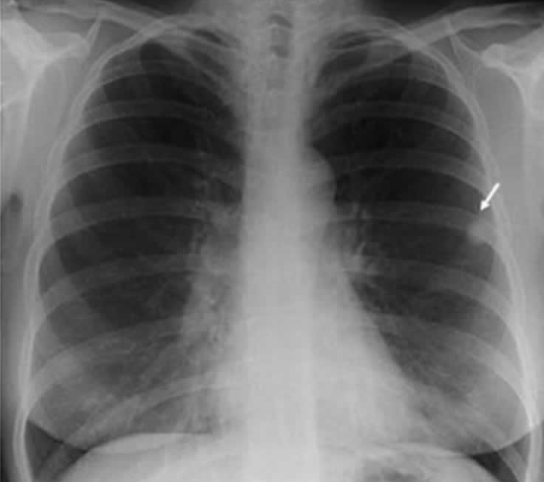

CXR상에 나타난 정보를 점수화하여 TB granuloma가 존재하는 환자의 분포를 추정하는 기계를 만든다고 하자. 아래 그림에서는 사진 우측에 보이는 화살표가 granuloma에 해당하는 영역이다.

- ML: 어떤 점수 x가 나온 CXR에 대해, granuloma 환자에서 그 점수가 나올 확률 P(x | granuloma)과 정상인에게서 그 점수가 나올 확률 P(x | ~granuloma)의 값을 비교하여 더 높은 것을 산출한다.

- MAP: 어떤 점수 x가 나온 CXR에 대해, granuloma일 확률 P(granuloma | x) 과 정상일 확률 P(~granuloma | x)을 비교하여 더 높은 것을 산출한다.

MAP에서 P(granuloma | x)에는 어떤 정보가 들어가 있는가? 가능도 P(x | granuloma)도 들어가 있지만, 사전 확률(prior)에 해당하는 P(granuloma)도 들어가 있다. 따라서, 기존에 granuloma 환자의 비율이 어느 정도 된다는 사전 정보가 있어야 사용할 수 있다. 또한 이 값에 따라 모델의 분류 기준이 바뀔 수 있다. 즉, MAP를 쓰면 이 모델을 대한결핵협회에서 사용할 때와 콜롬비아(2021 결핵 사망률 1위 국가)에서 사용할 때 분류 기준이 다르다. 반면, ML을 쓰면 P(granuloma)를 고려하지 않기 때문에 전 세계 어디서나 분류 기준이 같을 것이다.